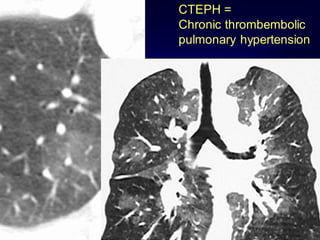

Mosaic Perfusion

Chronic pulmonary embolism

LOOK FOR

Pulmonary hypertension

idiopathic, cardiac disease, pulmonary

CTEPH =

Chronic thrombembolic